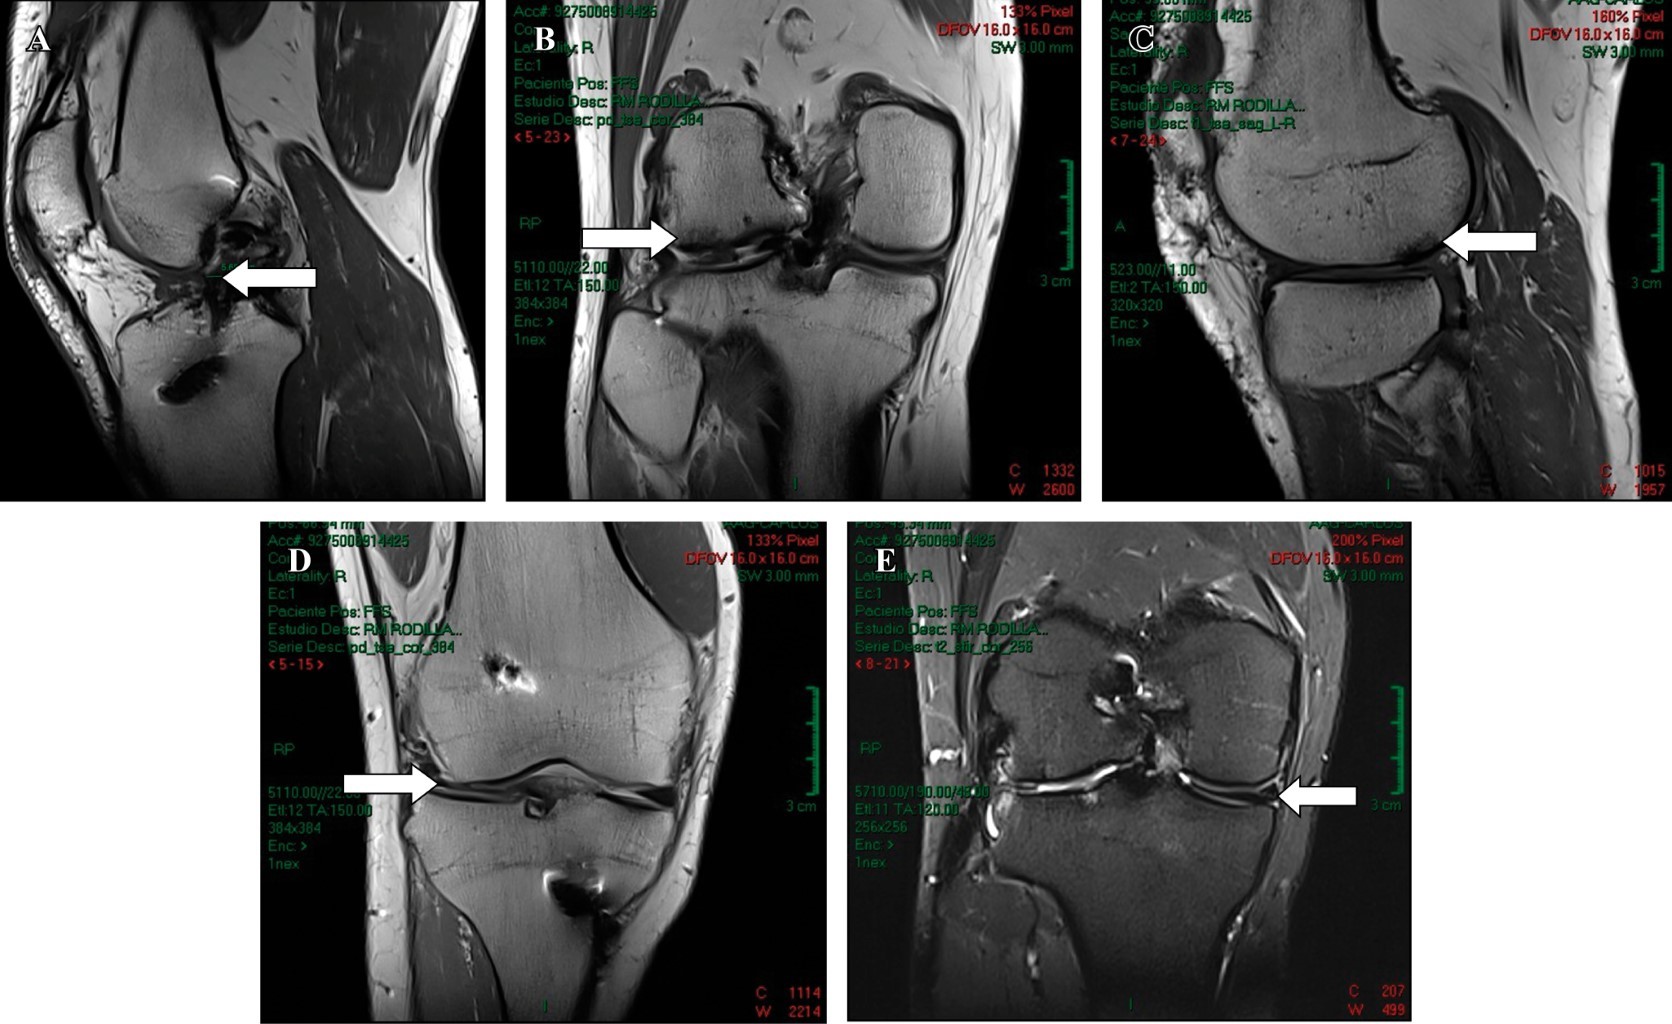

Lateral meniscus transplantation with allograft, a good alternative for the management of postmeniscectomy syndrome in young patients. Presentation of a case

Meniscal injuries represent one of the main causes of intra-articular knee pain, especially in young patients, athletes or those with a high demand for physical activity; representing a challenge for the arthroscopist surgeon due to the great complexity that some of these injuries can present. Currently, the advances that have been implemented in arthroscopy allow us to repair meniscal injuries that in the past were considered irreparable. Although our priority is to preserve as much of the meniscus as possible, there are cases in which the injury reaches such complexity that this is impossible, with partial or total meniscectomy being the only therapeutic option. In the United States, approximately 690,000 partial meniscectomies are performed each year. This situation makes us consider meniscal transplantation as a great therapeutic option for patients considered young enough for joint replacement. The ideal patient is a relatively young patient (between skeletal maturity and 50 years), who has a well-documented history of partial or total meniscectomy, pain well localized to the affected compartment, with failure to conservative treatment and without high-grade chondral defects. in a generalized way. We present the case of a 35-year-old male patient with a history of total meniscectomy of the right lateral meniscus seven years ago, who currently presents with a postmeniscectomy syndrome of the lateral compartment. Due to the clinical and demographic characteristics of our patient, as well as the findings in the imaging studies, meniscal transplantation with allograft represents an excellent alternative to alleviate the symptoms and slow down as much as possible the need for joint replacement as a definitive treatment.

Figure 1

Figure 2

Figure 3

Figure 4

Figure 5

Figure 6

Figure 7

Figure 8